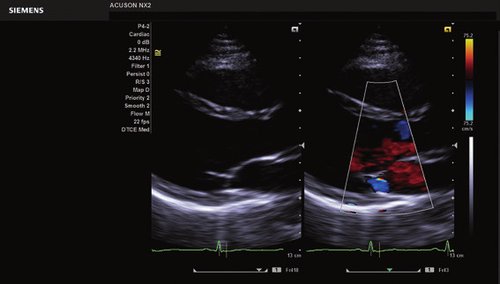

Das Ultraschallsystem Siemens ACUSON NX2 ist das mobile Einstiegssystem der nächsten Generation aus der Siemens ACUSON Produktlinie.

Als Mitglied der preisgekrönten Produktfamilie ACUSON NX verfügt die neue, sehr leichte und kompakte Plattform ACUSON NX2 über eine hochentwickelte Bildverarbeitungsarchitektur.

Sie bietet sowohl erstklassige Bildqualität auf dem größten Monitor ihrer Klasse als auch effiziente Workflows mit dem neuen taktilen Bedienfeld von Siemens. Das ACUSON NX2 eignet sich für eine Vielzahl von Untersuchungsverfahren im klinischen Alltag und ist die perfekte Wahl für die Standardbildgebung mit einem sehr guten Preis-Leistungsverhältnis.

Das Siemens ACUSON NX2 Ultraschallgerät ist ein auf Performance optimiertes Ultraschallsystem, welches eine durchdachte Lösung für eine Vielzahl an Anforderung bietet und eine optimale Leistung erbringt. Das Ultraschallgerät ist hochgradig produktiv und effizient und liefert zuverlässige Ergebnisse. Das ACUSON NX2 ist darauf ausgelegt, die besonderen Herausforderungen des klinischen Praxisalltags zu erfüllen, und die Erwartungen des Anwenders zu übertreffen. Darüber hinaus liefert das ACUSON NX2 die neuesten Technologien, die es zu einem aufrüstbaren, skalierbaren und intelligenten Ultraschallsystem machen, welches konsistente und eindrucksvolle Ergebnisse liefert. Dank einem Höchstmaß an Spitzenleistung, wird eine große Diagnosesicherheit erzielt, und ihre Bildgebungstandards werden auf ein neues Niveau geführt.

Das ACUSON NX2 Ultraschallsystem besitzt eine zukunftsfähige digitale Plattform mit nahezu unerreichter Bildqualität und sorgt für effiziente und zuverlässige Diagnosedaten. Die Vielseitigkeit des Ultraschallsystems wird mit einem großen kompatiblen Portfolio an Schallköpfen gedeckt, und so ist für jeden Anwendungsbereich etwas dabei. Die Bedienkonsole ist intuitiv aufgebaut und optimiert und erlaubt bis zu vier nach vorne gerichteten Schallkopfanschlüssen für eine enorme Effizienz und schnellen Workflow. So lassen sich bei der fetalen Bildgebung außergewöhnlich detailgetreue Darstellungen des Fetus im Gesicht zeigen oder durch die herausragende Farbdopplersensitivität bei der Darstellung der kleinen Gefäße des zystischen Schilddrüsenknotens kleinste Details erkennen. Weiterhin besticht das NX2 mit einfacher Aufrüstbarkeit bei wachsenden Anforderungen für Ihre zukünftigen Anwendungen und kompatible skalierbare Schallköpfe verringern ihren Kapitaleinsatz um bis zu 31 %.